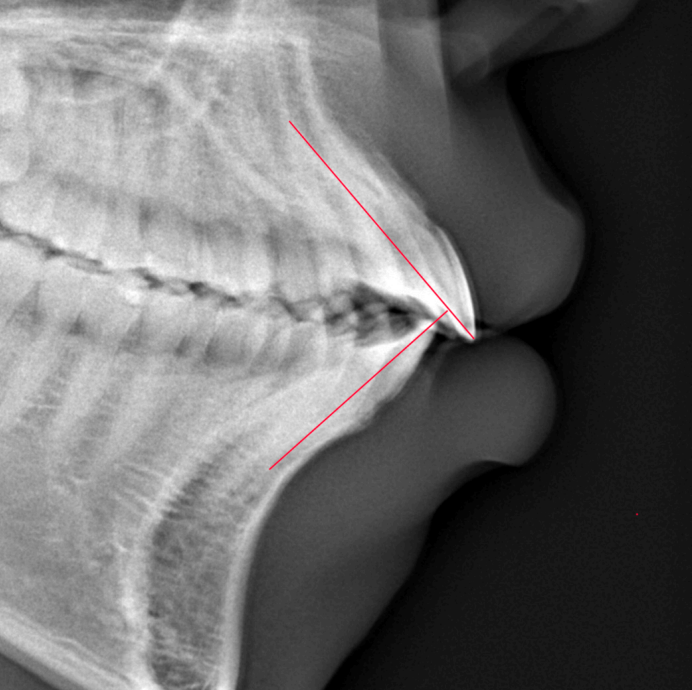

Before

| 症例分類 | 上下顎前突 |

|---|---|

| 主訴 | 前歯が出ていて、口が閉じにくい |

| 年齢 | 20歳0ヶ月 |

| 性別 | 男性 |

| 抜歯部位 | 上下顎両側第一小臼歯 |

| 使用装置 | 歯の表側からのマルチブラケットによる矯正装置 |

| 治療期間 | 2年10ヶ月 |

| 保定装置 | 取り外し式保定装置 |

| 費用 | 相談料0円、検査料55,000円 動的矯正治療費935,000円 調整料6,600円×28回分 保定装置料0円 |

| リスク・注意点 | 上下の個々の歯の大きさに対して上下の顎が小さく歯が並ぶスペースが不足したために上下の前歯が前方に傾斜して、上下顎前突が生じています。これらを改善するために、上下顎両側第一小臼歯を抜歯して、このスペースを用いて歯を排列しました。歯の動き方には個人差があり、予想された治療期間が延長する可能性があります。 治療中は矯正歯科装置が歯の表面に付いており、歯が磨きにくくなるため、むし歯や歯周病が生じるリスクが高まります。ハミガキを適切に行ってお口の中を常に清潔に保ち、さらに、かかりつけ歯科医に定期的に受診することが大切です。 顎間ゴムの使用状況、定期的な通院など、矯正歯科治療には患者さんの協力が必要であり、それらが治療結果や治療期間に影響します。 治療の経過によっては当初予定していた治療計画を変更する可能性があります。 歯を動かすことにより歯根が吸収することがあります。 保定装置の装着時間が十分確保できない場合、歯並びや、咬み合せの「後戻り」が生じる可能性があります。 |